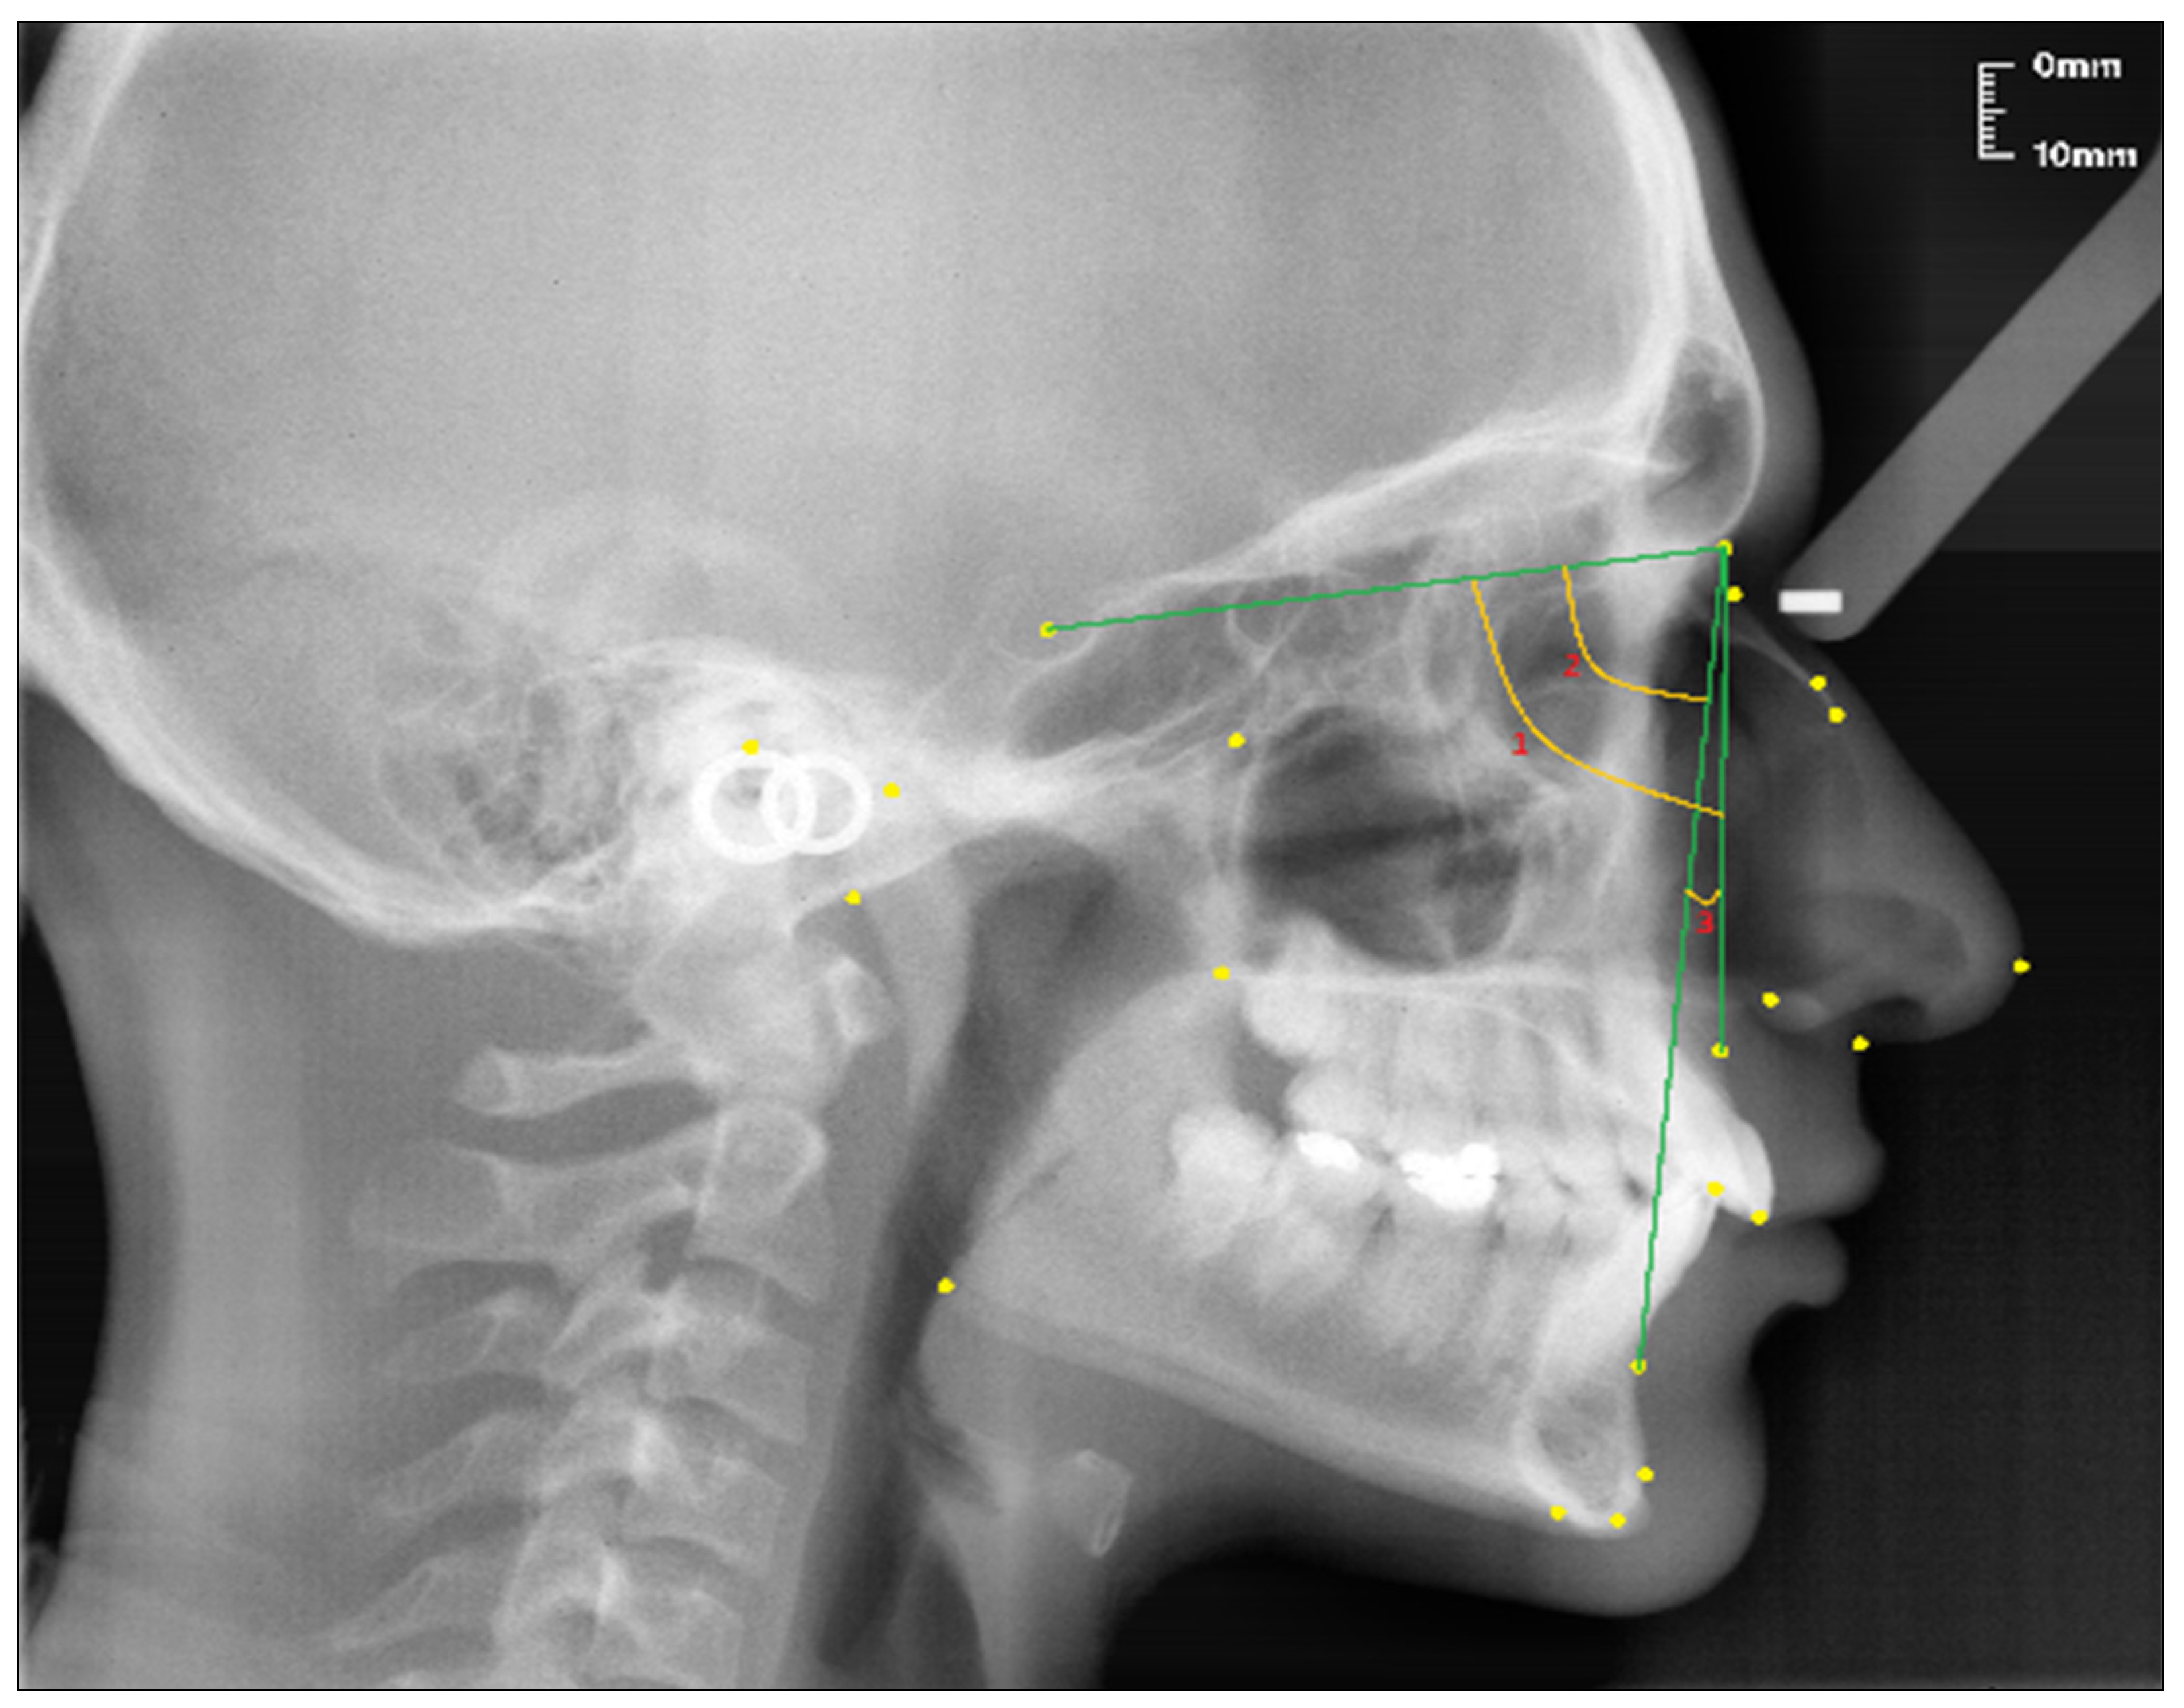

The points used in lateral cephalometric films to evaluate the nasal structure are as follows [1,30]. (see Figure 1)

Figure 1.

Points used in the study.

- Sella (S); the center of Sella turcica.

- Nasion (N); the most anterior point of the sutura frontonasalis and the deepest place of the recess in that region.

- Rhinion (R); the most anterior and inferior point on the tip of the nasal bone.

- Subspinal–point A; below the ANS point, the maxilla is the deepest point of the alveolar bone recess.

- Supramental–point B; deepest midline point on the mandible between infradentale and pogonion.

- Anterior nasal spine (ANS) point; the tip of the median, sharp bony process of the maxilla at the lower margin of the anterior nasal opening.

- N1 point; the most concave point of the nasal bone.

- N2 point; the most convex point of the nasal bone.

Linear measurements (see Figure 2):

Figure 2.

Linear measurements of the nasal profile used in the study.

- Nasion-Rhinion (N-R); the distance between the nasion and the rhinion points.

- Nasion-Anterior nasal spina (N-ANS); the distance between the nasion and the anterior nasal spina points.

- Rhinion-Subspinale (R-A); the distance between the rhinion and the subspinale points.

- Nasion-Subspinale (N-A); the distance between the nasion and the subspinale points.

Angular measurement (see Figure 3):

Figure 3.

Angular measurement of the nasal bone used in the study.

- Nasal Bone Concavity Angle (Nbone Angle); the posterior angle formed between the N1-N2 line and the N2-R line.

Figure 4.

Angular craniofacial skeletal measurements used in the study.

- SNA (°); the angle between the SN line and the NA line.

- SNB (°); the angle between the SN line and the NB line.

- ANB (°); the angle between the lines NA and NB.